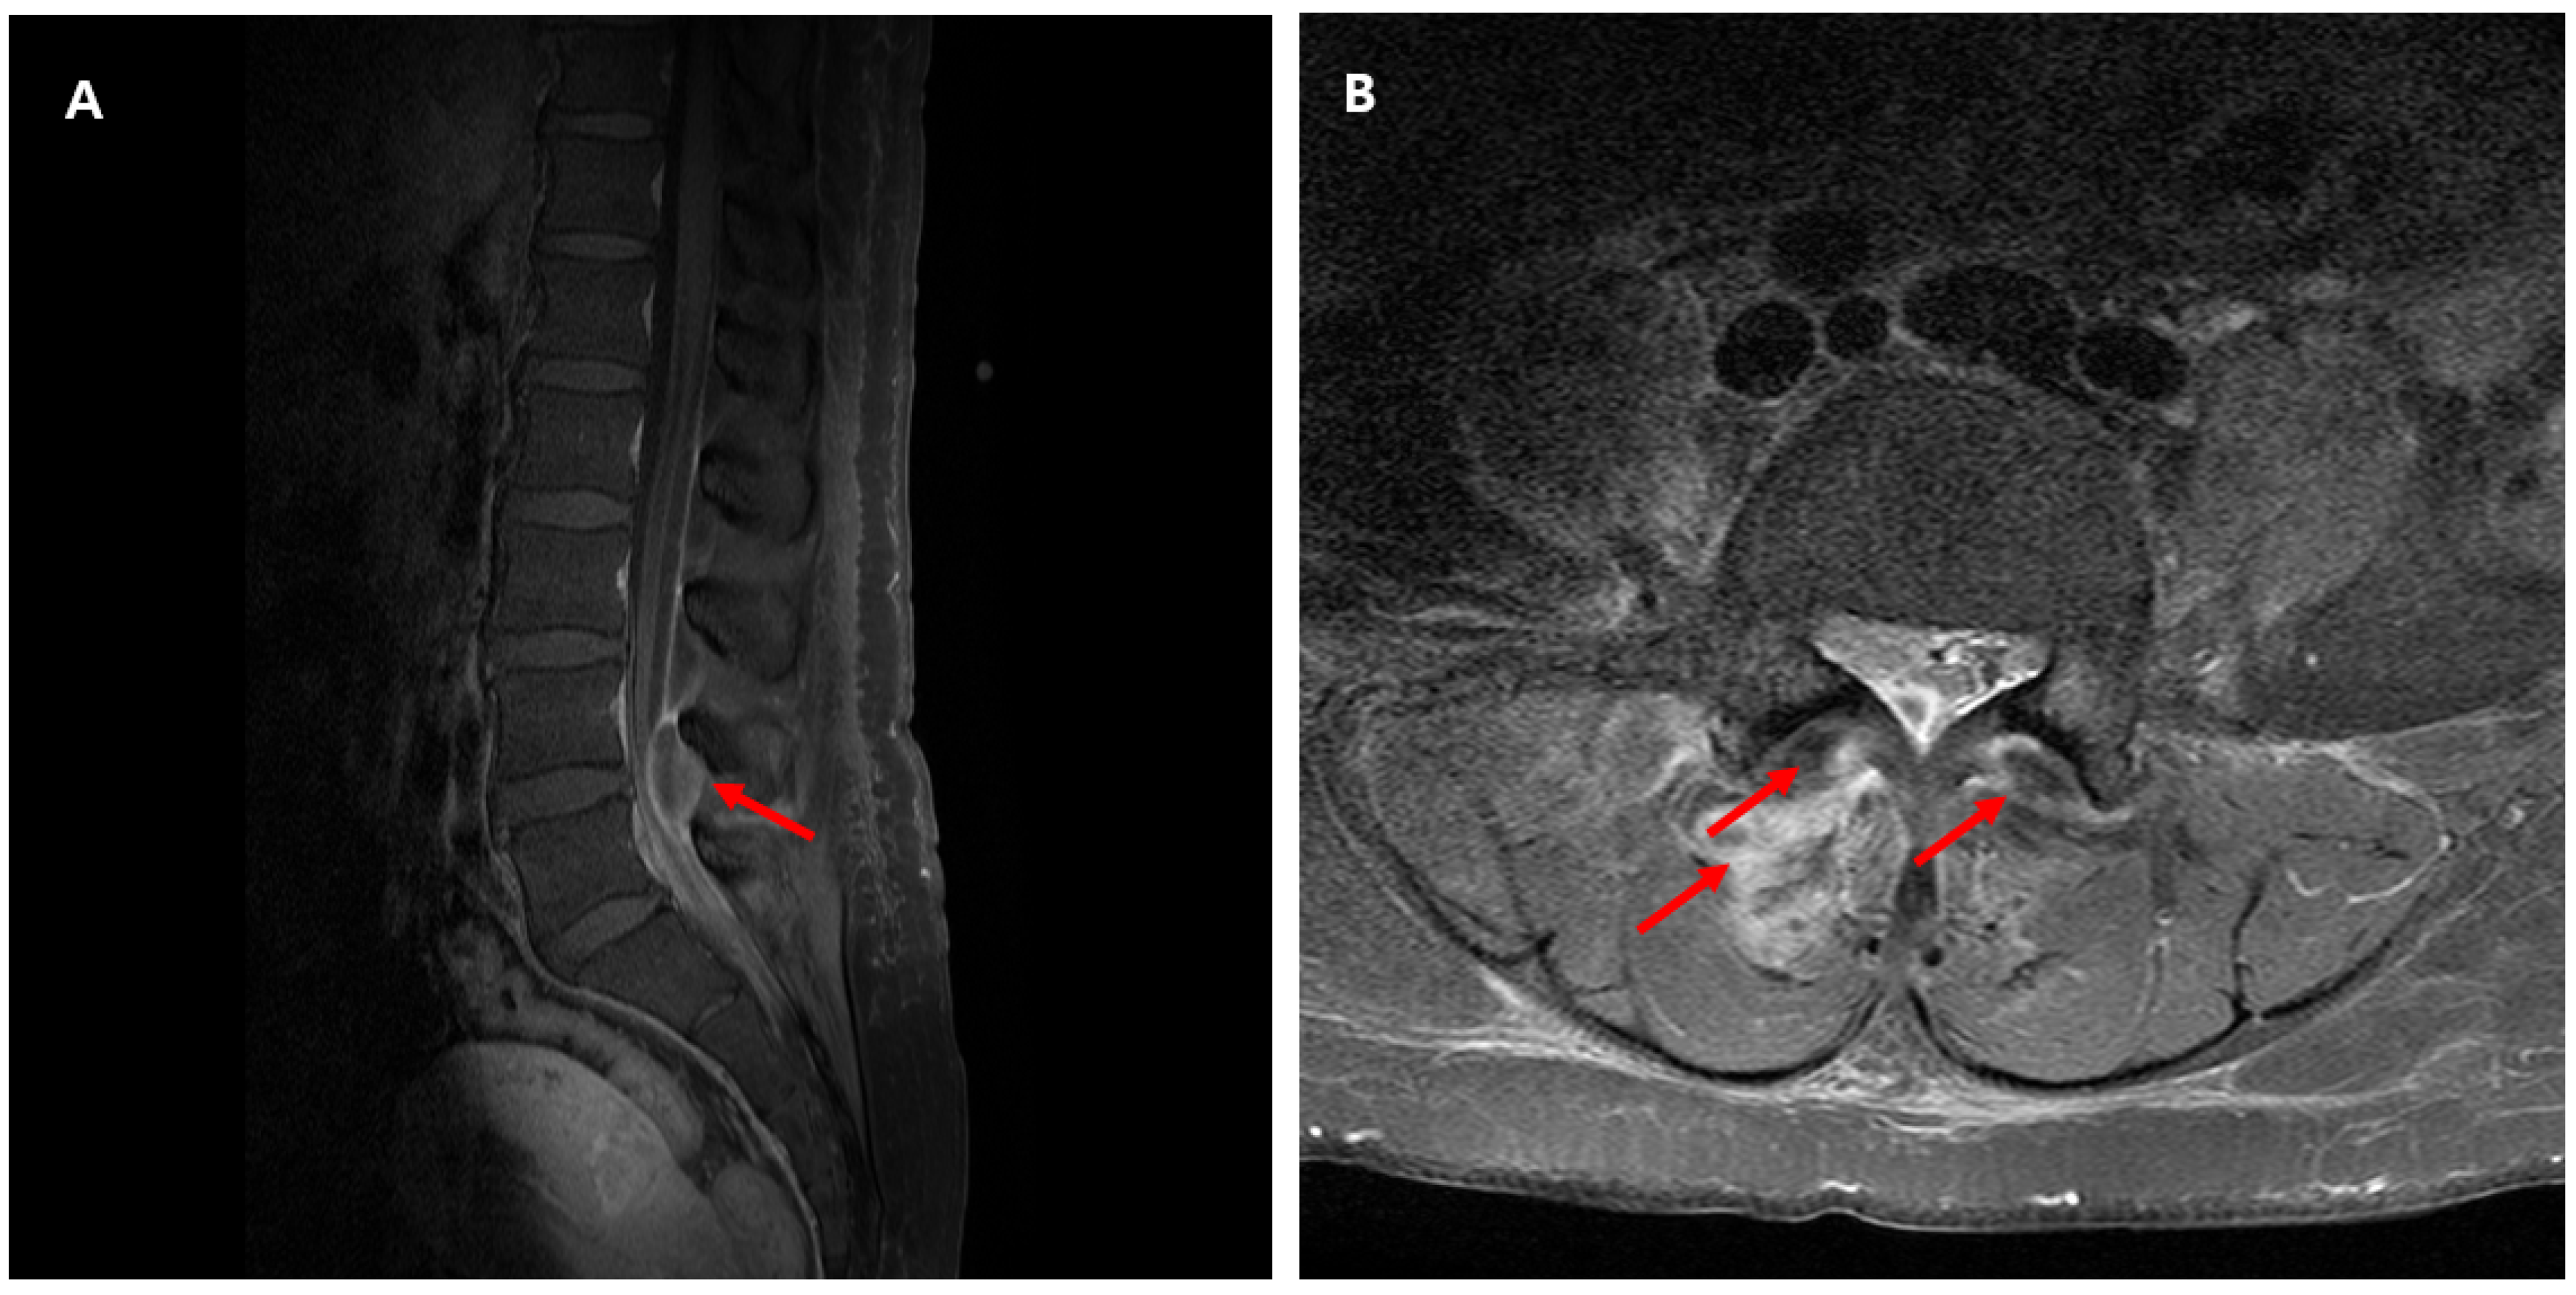

2. Case Presentation

| 3 | F/53 | Lumbar spine disc herniation | Right lower back pain with radiating pain in the right thigh Fever | No | L4-5 | None | None | No | Yes (HD 2) | Ceftriaxone (11 days) → levofloxacin (76 days) | Survived | No | This case |